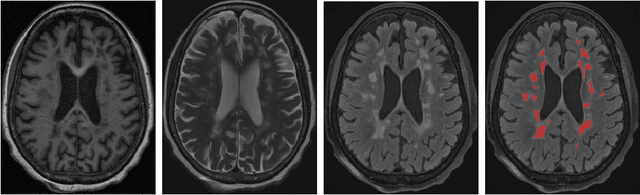

Abstract:Quantitative susceptibility maps from magnetic resonance images can provide both prognostic and diagnostic information in multiple sclerosis, a neurodegenerative disease characterized by the formation of lesions in white matter brain tissue. In particular, susceptibility maps provide adequate contrast to distinguish between "rim" lesions, surrounded by deposited paramagnetic iron, and "non-rim" lesion types. These paramagnetic rim lesions (PRLs) are an emerging biomarker in multiple sclerosis. Much effort has been devoted to both detection and segmentation of such lesions to monitor longitudinal change. As paramagnetic rim lesions are rare, addressing this problem requires confronting the class imbalance between rim and non-rim lesions. We produce synthetic quantitative susceptibility maps of paramagnetic rim lesions and show that inclusion of such synthetic data improves classifier performance and provide a multi-channel extension to generate accompanying contrasts and probabilistic segmentation maps. We exploit the projection capability of our trained generative network to demonstrate a novel denoising approach that allows us to train on ambiguous rim cases and substantially increase the minority class. We show that both synthetic lesion synthesis and our proposed rim lesion label denoising method best approximate the unseen rim lesion distribution and improve detection in a clinically interpretable manner. We release our code and generated data at https://github.com/agr78/PRLx-GAN upon publication.

Abstract:Background: Rim+ lesions in multiple sclerosis (MS), detectable via Quantitative Susceptibility Mapping (QSM), correlate with increased disability. Existing literature lacks quantitative analysis of these lesions. We introduce RimSet for quantitative identification and characterization of rim+ lesions on QSM. Methods: RimSet combines RimSeg, an unsupervised segmentation method using level-set methodology, and radiomic measurements with Local Binary Pattern texture descriptors. We validated RimSet using simulated QSM images and an in vivo dataset of 172 MS subjects with 177 rim+ and 3986 rim-lesions. Results: RimSeg achieved a 78.7% Dice score against the ground truth, with challenges in partial rim lesions. RimSet detected rim+ lesions with a partial ROC AUC of 0.808 and PR AUC of 0.737, surpassing existing methods. QSMRim-Net showed the lowest mean square error (0.85) and high correlation (0.91; 95% CI: 0.88, 0.93) with expert annotations at the subject level.